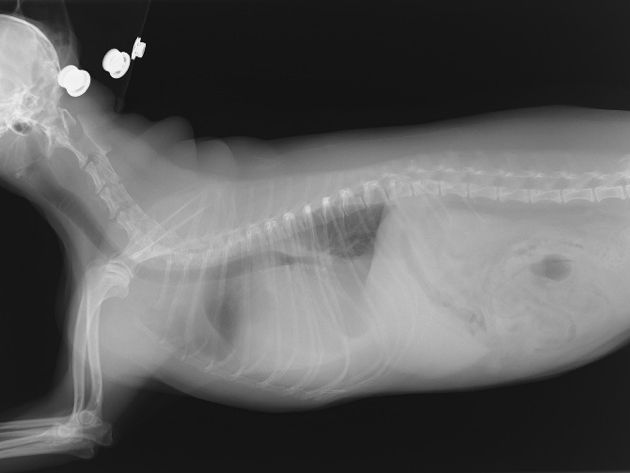

手術前の心臓のエコー画像・レントゲン画像・貯留した心嚢水により心臓が圧排されている。